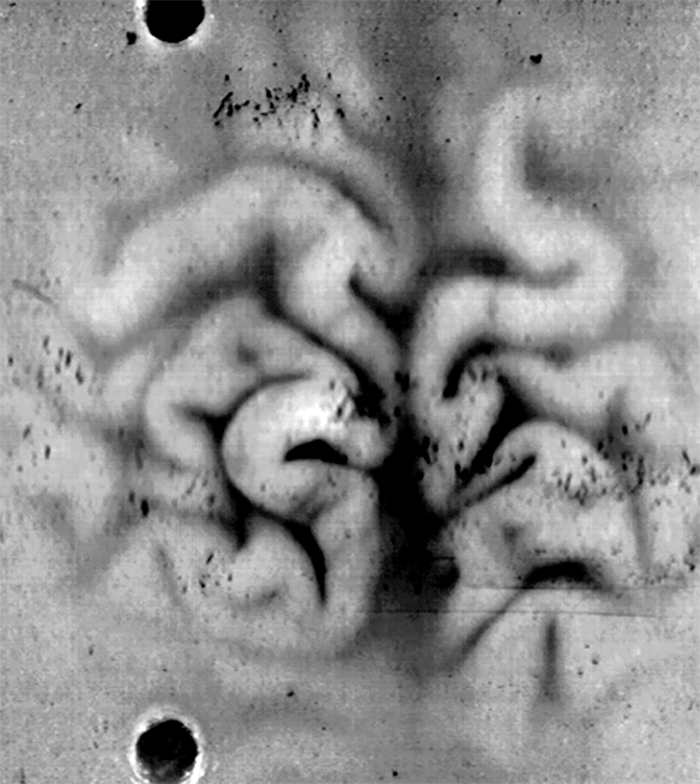

Brain Slices